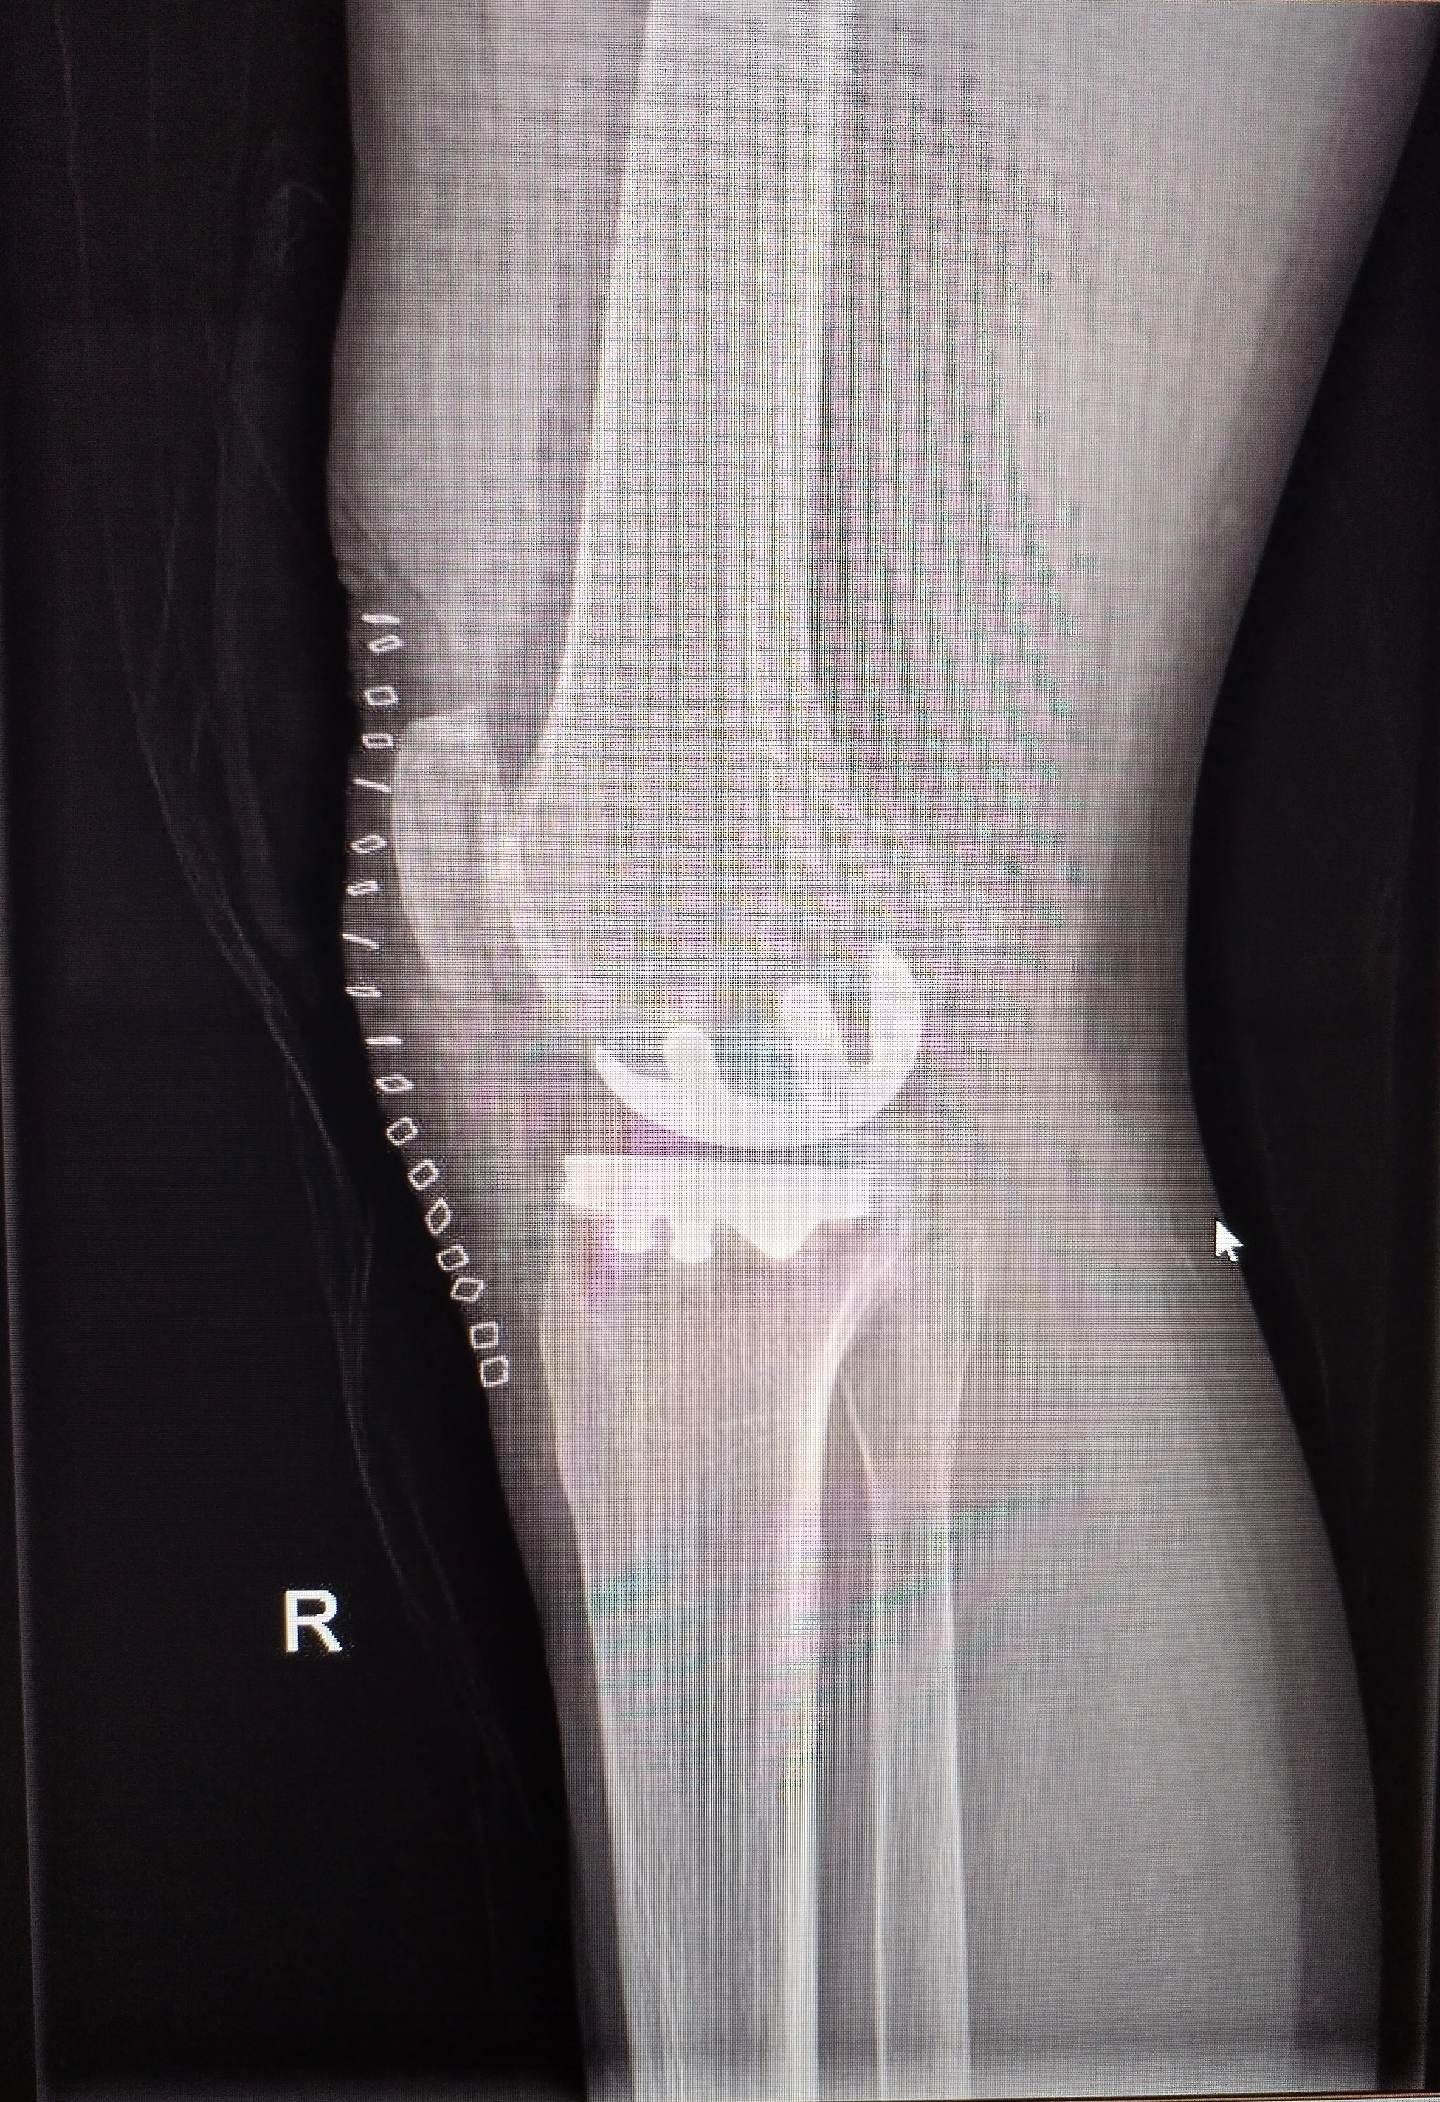

UKA单髁置换。膝关节骨关节炎,同期双侧单髁置换,术后四天出院,快速康复,省医关节外科🌹